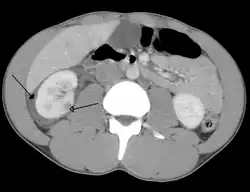

![]() إصابة بطنية أدت إلى رضة (كدمة) في الكلية اليمنى (السهم غير المظلل الرأس) وإحاطة الكلية بالدم (السهم المظلل الرأس) كما ترى بواسطة التصوير المقطعي المحوسب. إصابة بطنية أدت إلى رضة (كدمة) في الكلية اليمنى (السهم غير المظلل الرأس) وإحاطة الكلية بالدم (السهم المظلل الرأس) كما ترى بواسطة التصوير المقطعي المحوسب. | |